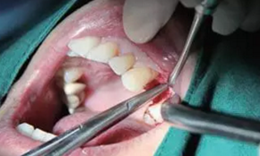

翻瓣與植入種植體

注意翻瓣不能太大,只需將窩洞頂端及周邊充分暴露即可。檢查種植窩洞頂端邊緣的骨壁情況,將窩洞頂端的高點(diǎn)去除,防止其干涉愈合基臺的就位。植入種植體植入時通過扭力扳手來確定最終的植入扭力,并判斷是否合適放置愈合基臺,也可以通過松動度測量儀測量ISQ值來判斷。

圖4 小翻瓣暴露窩洞頂端并去除高點(diǎn)